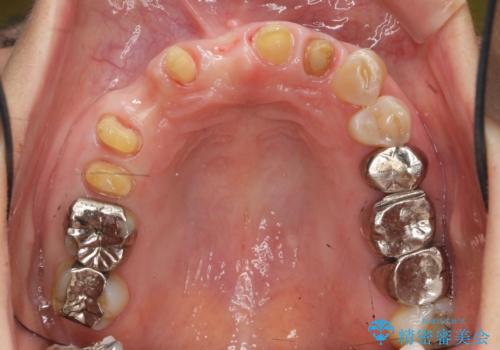

過度な咬合力 歯ぎしりで抜けた歯の欠損補綴

- 前歯を噛みしめにより失い、さらに犬歯もグラグラになり全く噛めなくなり改善を求めて来院されました。

過度な力がかかり周囲の骨に高度な吸収が見られた犬歯は抜歯し、機能・審美性の回復をより咬合力に対して抵抗力のあるブリッジ補綴にて対応します。